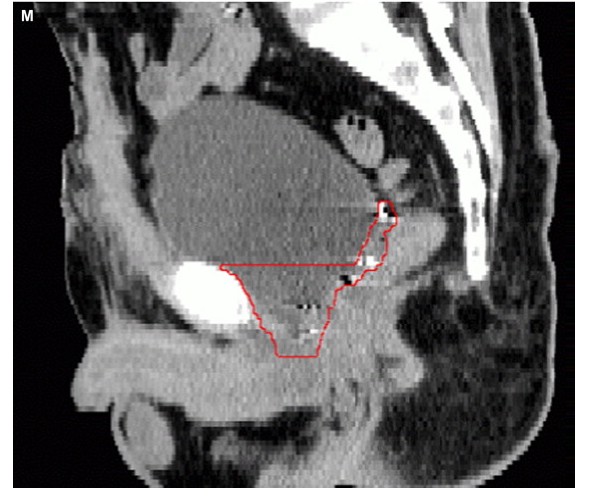

NCCN guidelines. A Typical technique from RTOG P-0011 which compares postOP radiation

alone (63 - 66Gy) with radiation plus two years of Lupron, the radiation ports are

shown here and here and here. The RTOG has

a contouring site

here, other images for contouring: